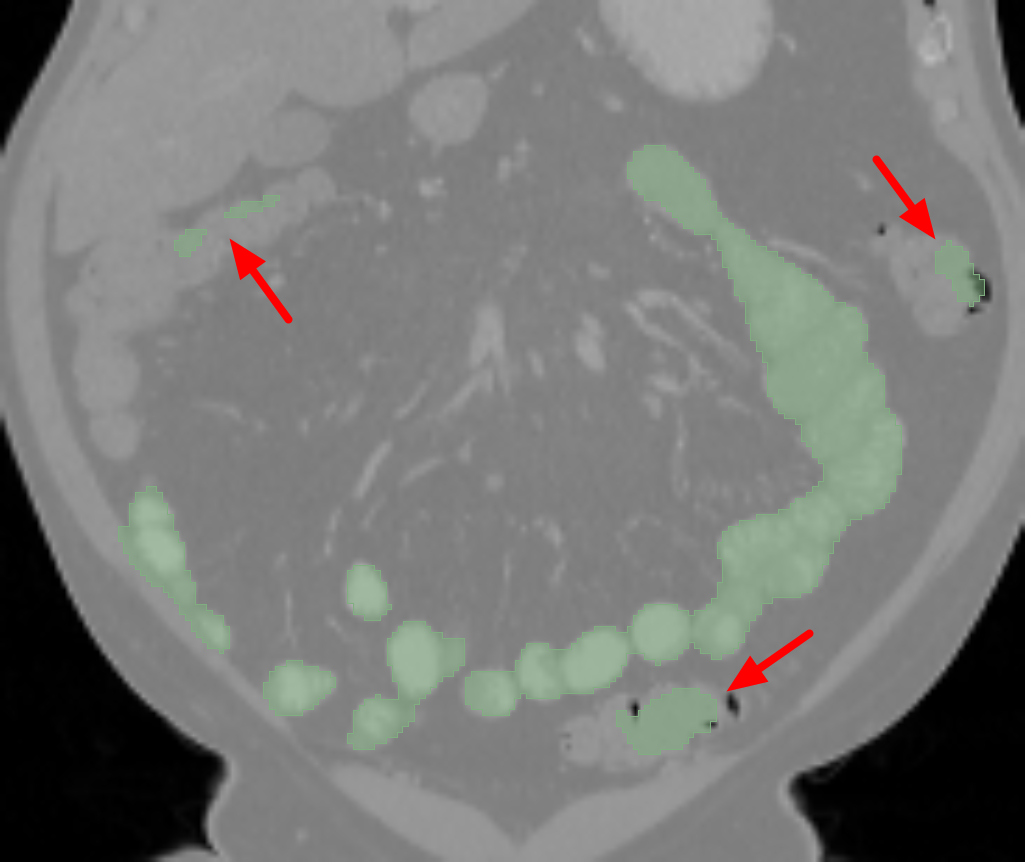

The small bowel has a cylindrical shape but also has many touchings with different parts along its path, which makes it have variable topologies across patients and time. It is inappropriate to apply a constant topological constraint to such organs. Fig. 1 shows an example of the small bowel path covered by the lumpy ground-truth (GT) segmentation.

GT labels were achieved by an experienced radiologist using 3DSlicer111https://www.slicer.org [6] based on the following steps. Firstly, the path of the small bowel is drawn as interpolated curves which connect a series of manually placed points inside the small bowel. Secondly, we grow the curves using a margin of and threshold it again using a Hounsfield unit (HU) range of . Manually drawn air pockets, which have much lower HU values, are also added during the second step. Produced errors are manually fixed in the final step. We note that this annotation procedure took one or two full days for each volume. Finally, the dataset includes the two types of labels, which are the path and segmentation of the small bowel as shown in Fig. 1.

Fig. 3 shows example segmentation results. The proposed method eliminates false positives on the large bowel by the help of the applied topological constraint. Fig. 4 further clarifies the effectiveness of the proposed method by presenting 3D rendered segmentations. The proposed method produces a more topologically correct segmentation of the small bowel with fewer false positives. Fig. 5 presents example barcode diagrams, which again show the reduced numbers of connected components and holes within the segmentation result of the proposed method.